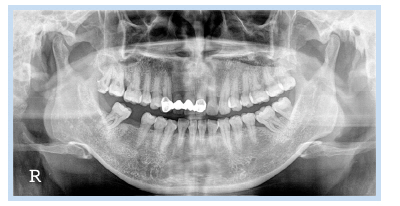

37세 여성이 오래 전에 발거한 하악 우측 제1대구치 위치의 무치악 부위 임플란트 식립 및 수복을 위하여 내원하였다. 파노라마 방사선 사진에서 하악 우측 제1대구치를 발치한 무치악 부위에 방사선 불투과상을 보이는 잔존 치근으로 추정되는 것이 관찰되었다(Fig. 13). 잔존 치근은 그대로 남겨둔 채로 임플란트를 식립하기로 계획하였다. 국소마취하에 치조정 절개 및 골 점막 피판을 거상하여 직경 4.5 mm 높이 10 mm의 임플란트를 식립하였다. 치유 지대주를 연결한 후 fixture의 근심 면의 협측에 골열개가 존재하여 분말형 자가치아골이식재를 이식하였다. 피판을 재위치시키고 4-0 Vicryl로 봉합하였다. 1주 후 봉합사를 제거하였고 치근단 방사선 사진을 촬영하였다(Fig. 14). 임플란트 식립 3개월 후에 최종 보철물을 장착하였고, 임플란트 식립 5개월 후 근심 측 식편압입을 호소하여 보철물을 다시 제작하여 장착하였다. 임플란트 식립 47개월 후에 촬영한 치근단 방사선 사진을 통해 안정적으로 임플란트가 유지되고 있음을 관찰할 수 있었다(Fig. 15, 16).

Fig. 13. Preoperative panoramic radiograph of a 37-year-old female patient. Implant placement was planned at right mandibular 1st molar area. Radiopaque image is observed at mesial side of #47.

Jun-Bae Sohn et al. : Implant Placed in Contact with Retained Root: Case Reports. Implantology 2016